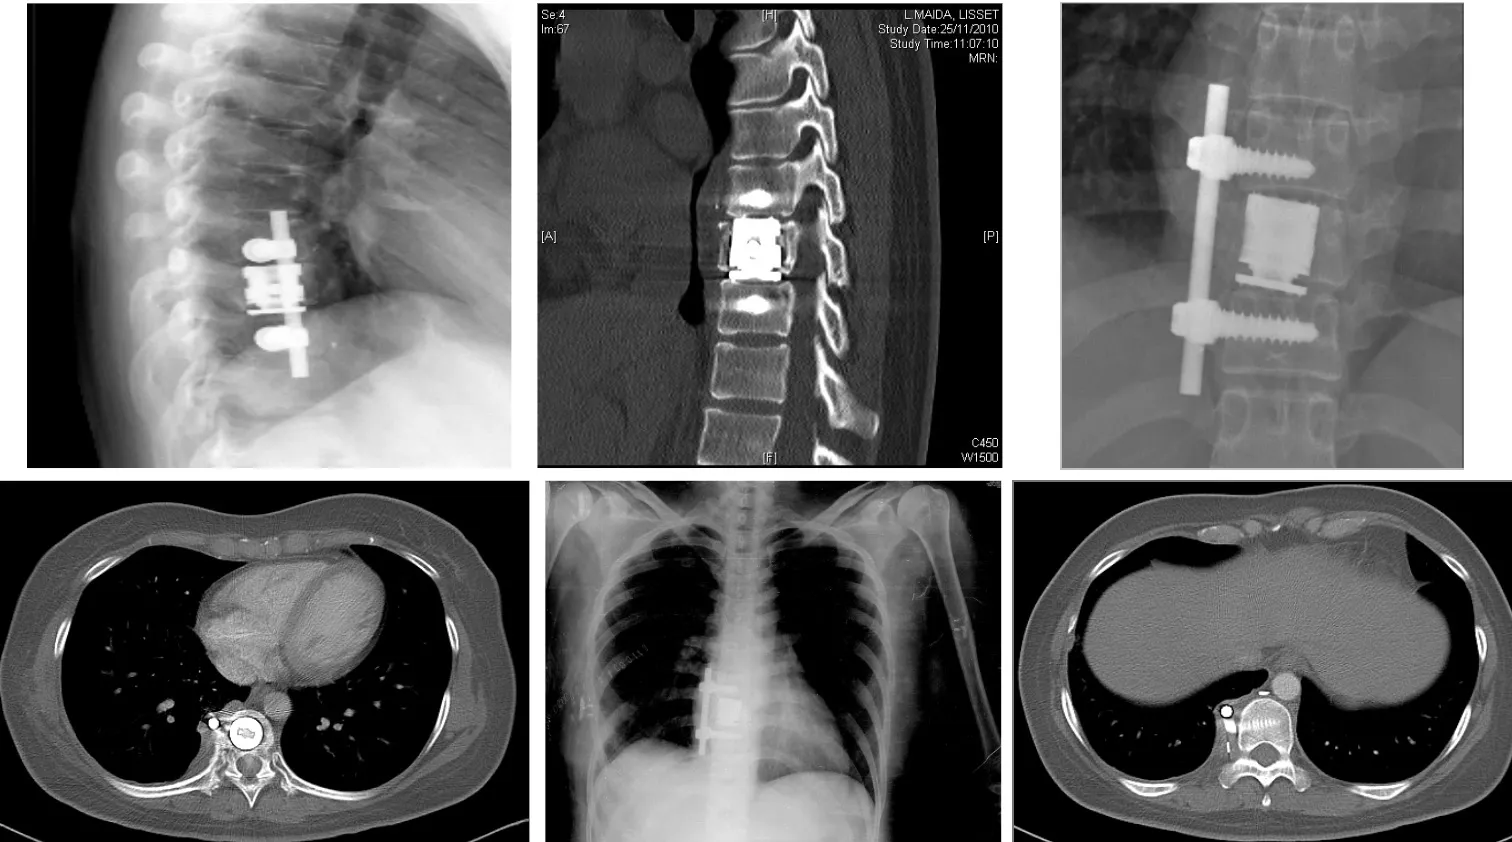

- Estabilización: restaurar la estabilidad de la columna mediante instrumentación con tornillos y barras, y en ocasiones con injertos óseos o cajas intersomáticas.

Técnicas quirúrgicas y resultados

Los estudios han demostrado que los abordajes dirigidos al foco infeccioso obtienen mejores resultados que las técnicas de descompresión simple:

- Laminectomías descompresivas sin fusión: resultados satisfactorios en 57-66% de los casos. Esta técnica, consistente en retirar las láminas vertebrales posteriores sin estabilizar, presenta resultados subóptimos.

- Desbridamiento y fusión posterior: acceso por la parte posterior de la columna con limpieza del foco y estabilización mediante tornillos pediculares. Resultados exitosos en el 97% de los casos.

- Abordaje y fusión anterior: acceso directo al foco infeccioso por delante, permitiendo una limpieza exhaustiva y colocación de injerto o caja intersomática. Resultados exitosos en 82-100% de los casos.

Estos datos confirman que el tratamiento quirúrgico debe ser agresivo en el sentido de abordar directamente el foco infeccioso y proporcionar estabilización adecuada, evitando técnicas de descompresión simple que han demostrado resultados inferiores.